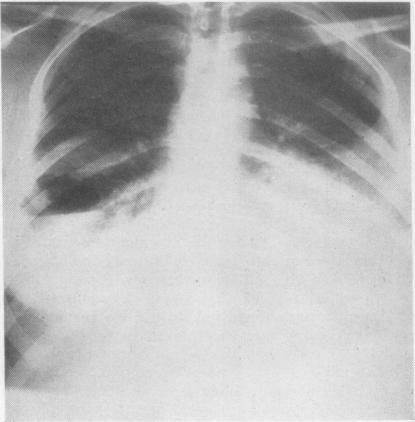

GINGELL J C

Thorax. 1965 May;20(3):261-9. doi: 10.1136/thx.20.3.261.